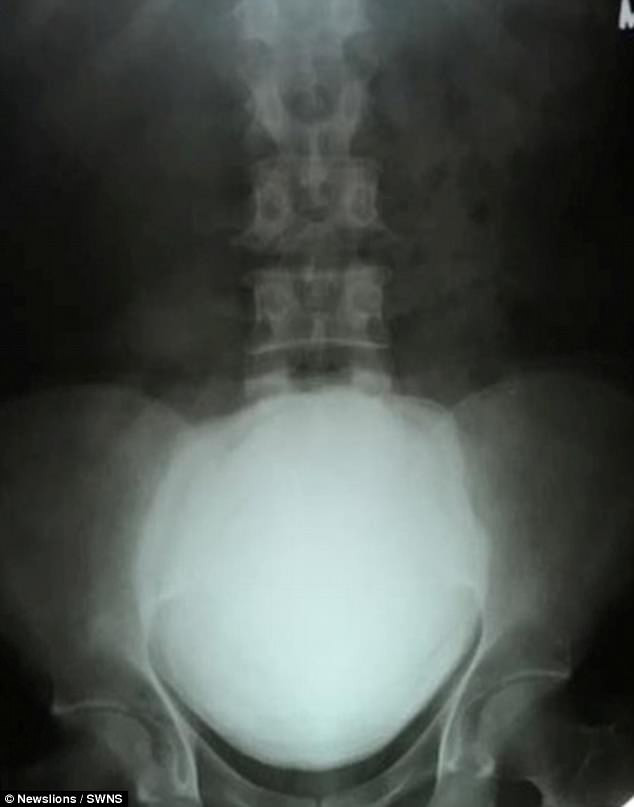

Ảnh X quang cục sỏi thân khi còn trong người của của Maheshbhai (Ảnh: Newslions)

Cảm thấy đau đớn bất thường xảy ra ngay trong đêm, Maheshbhai đã được đưa tới bệnh viện, nơi anh được chụp X quang và sử dụng kháng sinh trước khi được đưa đi phẫu thuật.

Các bác sĩ đã vô cùng kinh hãi khi phát hiện một viên sỏi thận có kích thước 11.5cm x 17 cm trong bàng quang của anh ta, khiến họ phải mất một tiếng rưỡi đồng hồ để lấy nó ra.

Cục sỏi thận khổng lồ nặng 1.4 kg, có kích thước 11.5cm x 17 cm (Ảnh: Newslions)